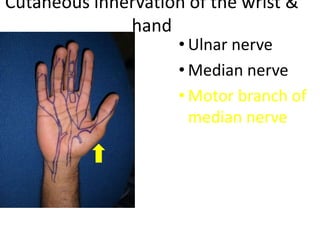

- Naming the bones, joints, tendons, nerves and skin landmarks of the hand and wrist.